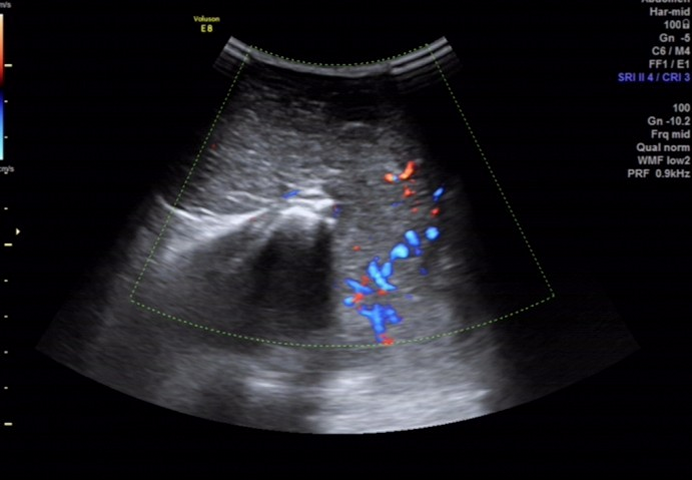

骶尾部皮下软组织层内探及一范围约 145×98×107mm 的低回声包块,围绕骶骨生长,部分向盆腔内生长,与周围其他组织分界清楚,内部回声欠均匀, CDFI:内见多个条状血流信号, PW 检测:呈动脉频谱, RI:0.72 。

图 3 CDFI:包块内见多个条状血流信号